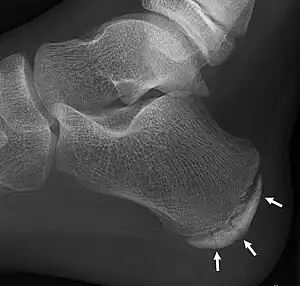

| X-ray of the foot of an 11-year-old child,showing sclerosis and fragmentation of the calcaneal apophysis. This is a sign of low sensitivity and specificity of Sever's disease, because those with Sever's disease may not have it, and this appearance is also present in feet without pain. | |

Children with calcaneal apophysitis commonly complain of pain at the back of the heel. This pain increases with jumping and some running sports. Sometimes, the pain makes children limp and may result in poor sports performance or them not wanting to participate in some sports. The back of the heel is never swollen or red, unless there has been shoe rubbing. When the back of the heel is squeezed from the inside and outside, children with calcaneal apophysitis will report pain. Foot radiographs are not needed to diagnose calcaneal apophysitis as the growth plate can look similar with or without pain. Health professionals should only refer for imaging when the symptoms don't match with the usual presentation or there has been an injury that has resulted in heel pain. Therefore, the diagnosis of Sever's disease is primarily from history and physical assessment.[5]